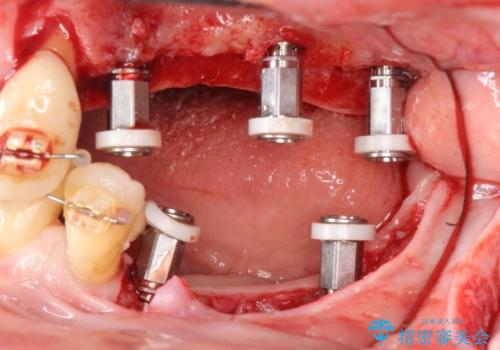

[前歯の歯根吸収] 前歯審美セラミックブリッジの製作

X線撮影より、歯根が吸収し残すことができない歯を抜歯、ブリッジによる審美性の改善を計画します。

![[前歯の歯根吸収] 前歯審美セラミックブリッジの製作の治療中](https://seimitsushinbi.jp/wp/wp-content/uploads/2020/12/8e350a781af946a6f1dd75a138446a00-500x350.jpg?v=1608091922)

![[前歯の歯根吸収] 前歯審美セラミックブリッジの製作の治療中](https://seimitsushinbi.jp/wp/wp-content/uploads/2020/12/a03f6281cfa6e6f92be9b80a2cd4b5b3-500x350.jpg?v=1608091926)

![[前歯の歯根吸収] 前歯審美セラミックブリッジの製作の治療中](https://seimitsushinbi.jp/wp/wp-content/uploads/2020/12/60fc4e478a621dfbf33cbe0817bdb0f6-500x350.jpg?v=1608091918)

![[前歯の歯根吸収] 前歯審美セラミックブリッジの製作の治療中](https://seimitsushinbi.jp/wp/wp-content/uploads/2020/12/7cfc03cc801b1352f0439ca6114e5bee-500x350.jpg?v=1608091929)

![[前歯の歯根吸収] 前歯審美セラミックブリッジの製作の治療中](https://seimitsushinbi.jp/wp/wp-content/uploads/2020/12/83219aeed9296afa864e0b224fdf6071-500x350.jpg?v=1608091914)

![[前歯の歯根吸収] 前歯審美セラミックブリッジの製作の治療中](https://seimitsushinbi.jp/wp/wp-content/uploads/2020/12/d37590a7f6cc409cc0a269e4c71e7658-500x350.jpg?v=1608091911)